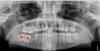

На снимке отмечены крестиком удаленные зубы (6 - удален давно,7,8 недавно)...хочу ставить протезы на их место..нужно что-то сделать сверху...поскольку 5 криво растет и ушел на небо, а 6 опустился вниз, потому что 6-ка отсутствовала давно...я так понимаю на такую кривоту протезы не поставишь? или поставишь?

1) можно ли выровнять 5-ку и подпилить 6-ку? это вообще реально или правильнее сделать что-то другое? (удалять не предлагайте-люблю свои зубы)